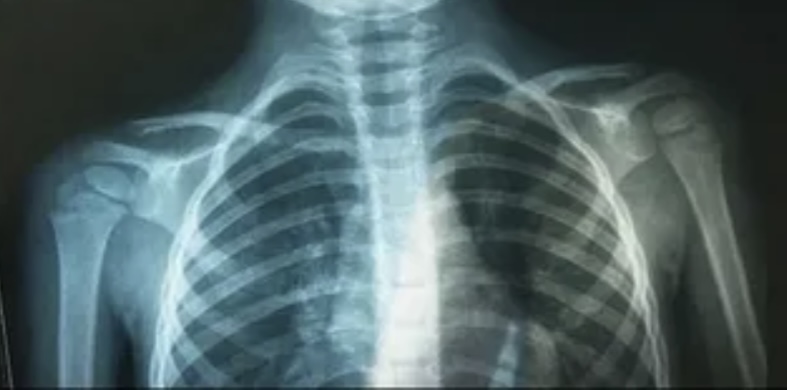

Здоровье сердца: защита начинается с детства

Стартовала неделя осведомленности о заболеваниях сердца. Она проводится в честь Международного дня осведомленности о пороках сердца, который отмечается 14 февраля.

«Пороки сердца — это аномалии строения сердца, которые могут быть врожденными или приобретенными, то есть развивающимися в течение жизни. Они связаны с нарушением структуры сердечных клапанов, основных сосудов сердца или внутрисердечных перегородок», — пояснила доктор.